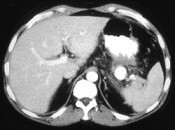

- 单项选择题男,36岁, 反复剑突下胀痛5年,加重伴间断性呕血、黑便3年, 有6年慢性胰腺炎病史,CT检查如图, 最可能的诊断是  (    )

- A、脾血管瘤伴慢性胰腺炎

- B、脾动脉瘤伴慢性胰腺炎

- C、脾假性动脉瘤伴慢性胰腺炎

- D、胰腺转移瘤伴慢性胰腺炎

- E、胰腺癌伴慢性胰腺炎